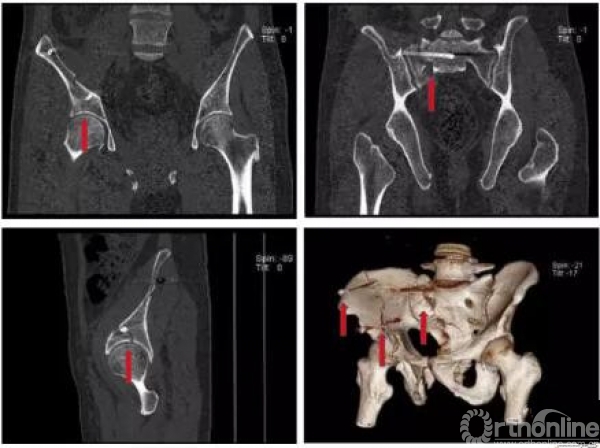

术前骨盆CT三维重建(2017.09.17)

术前骶尾椎CT三维重建(2017.09.17)

骨盆AO和Tile分型,以及基于骨折的受伤机制和稳定性Young and Burgess分型:APC LC(lc-II型)、VS、CM;髋臼两类十型(前柱合并前壁);骶骨骨折Dennis分型(II区)

骨折移位方向的准确判断(五种+混合)

基本类型:上移、外翻、内翻、旋前、旋后;以及混合型